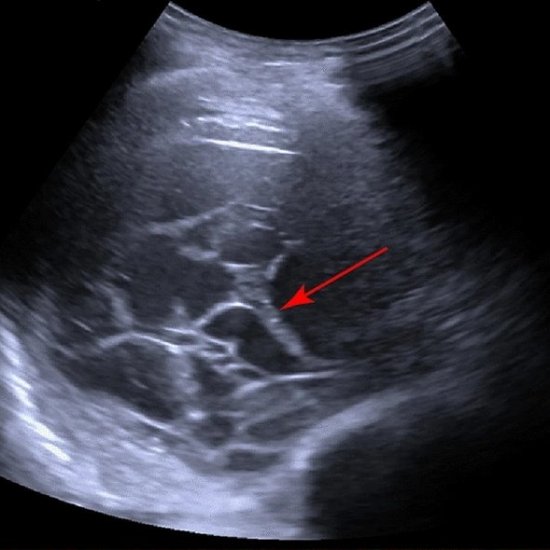

Has organ imaging using ultrasound arrived at the same level as cross-sectional imaging? At the annual conference of the German Society for Internal Medicine (DGIM), PD Dr Corinna Trenker presented new technological developments and their diagnostic ... |